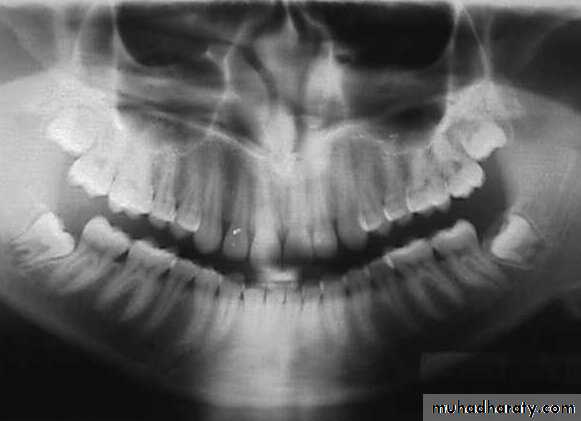

Developing root